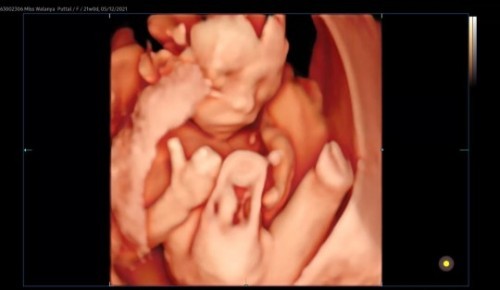

25วีค เท่ากับกี่เดือนคะ หมอ นัดแม่ๆคลอดเดือนไหนกัน ตรงไหมคะ

4 วีค = 1 เดือน แม่ 25 วีค = 6 เดือน 1 วีคค่ะ